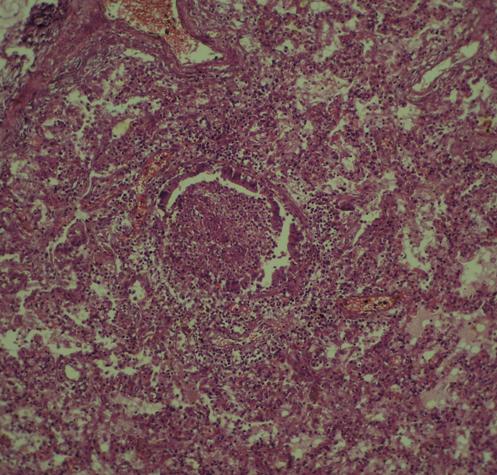

如其他肺炎,球形肺炎的病理是炎性渗出及水肿,通过肺泡向周围离心性扩散而致。